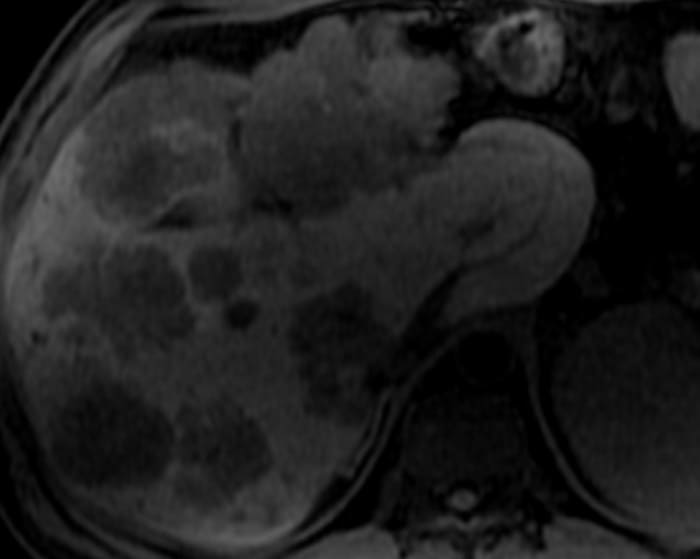

Di căn gan

» Thông tin: Nam giới – 37 tuổi.

» Lâm sàng: Tiền sử K đại tràng.